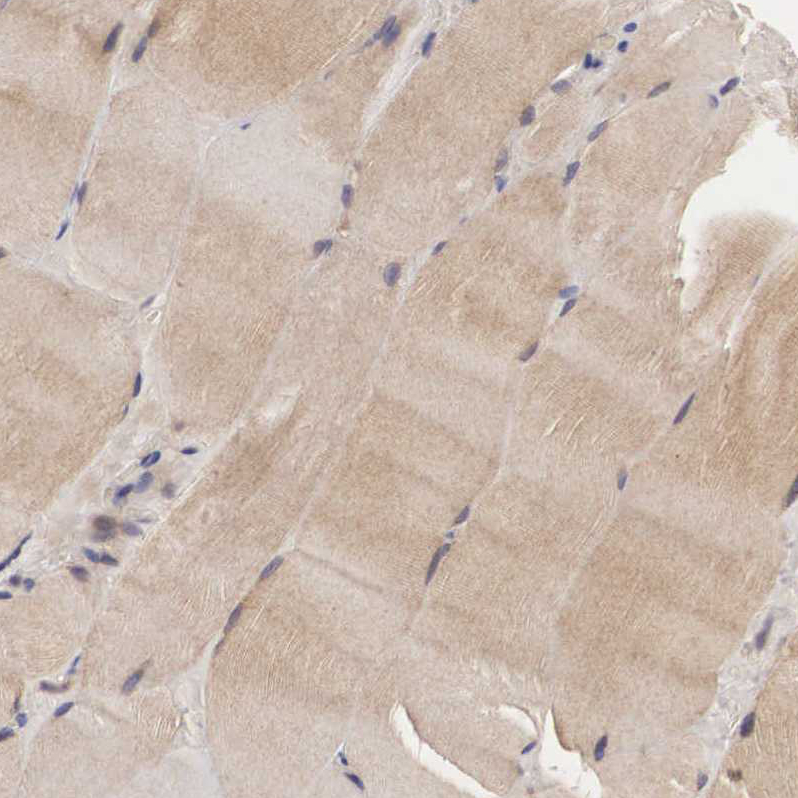

Immunohistochemical staining of human skeletal muscle shows moderate cytoplasmic positivity in myocytes.